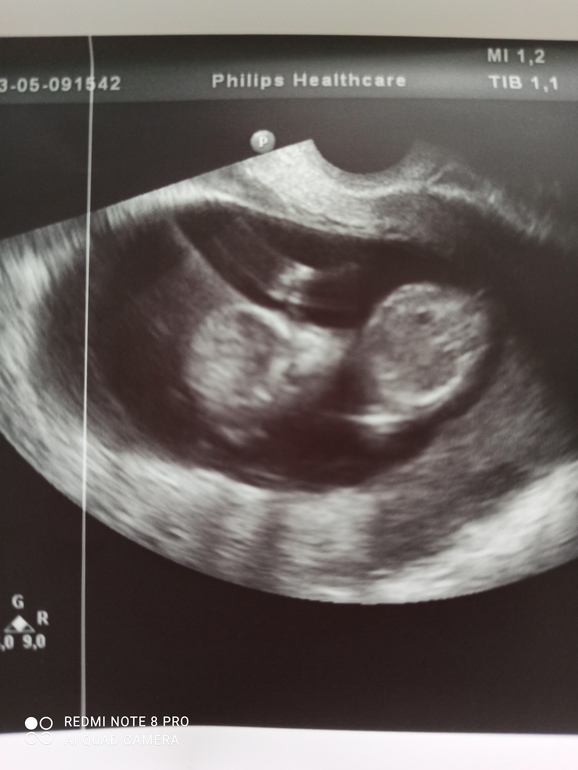

УЗИ, КТГ, доплерВрач предположила пол малыша, но не точно, виднеется на последнем фото, между ног что-то торчит, но на этом сроке это могут быть так ярко выражены половые губы. Всё в норме, можно спокойно ждать скрининг 10 марта в Самарском областном медико- генетическом центре.

Как думаете, это половой член или половые губы?

В 12 недель можно разглядеть первые различия - у мальчиков на половом бугорке будет линейное образование посередине, а у девочек видно 4 параллельные линии. Линейное образование у мальчиков - это будущие мошонка и пенис, а 4 параллельные линии у девочек - это будущие половые губы.